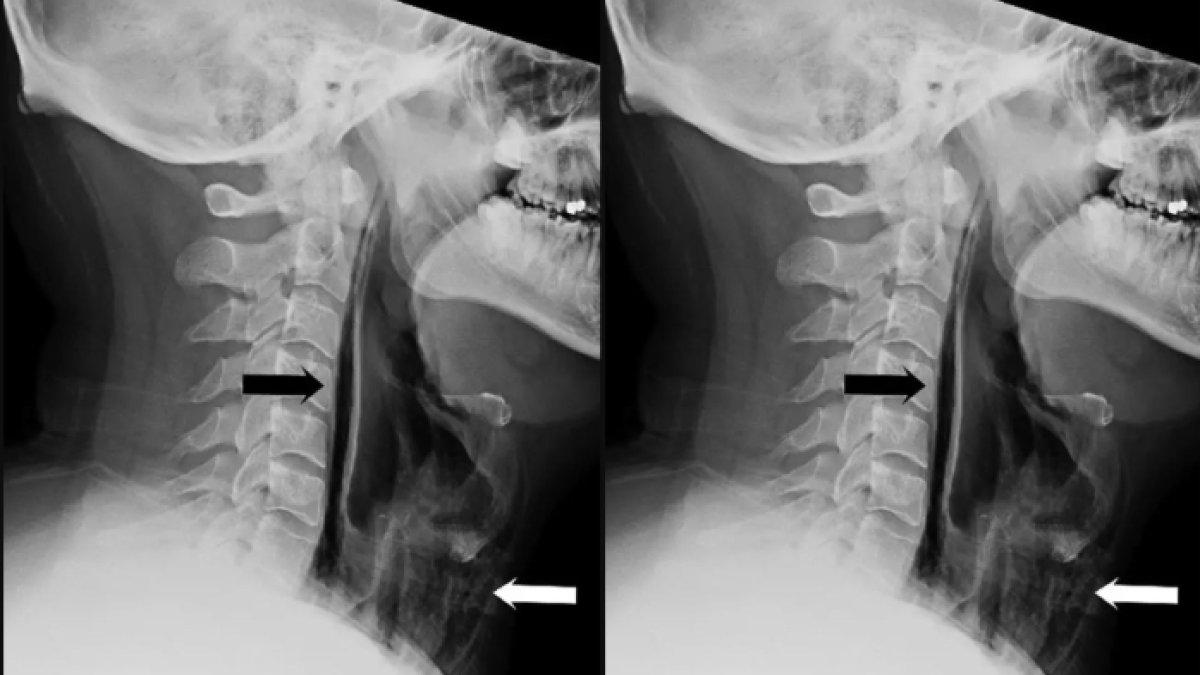

Setelah pemeriksaan fisik, tenaga kesehatan menemukan bengkak dan nyeri di lehernya dengan sinar-X.

Kemudian mengungkapkan bahwa garis-garis udara telah terperangkap di bagian jaringan tenggorokan pria itu.

Kantung udara yang terperangkap ini ada, berarti pria itu telah merobek tenggorokannya sendiri.